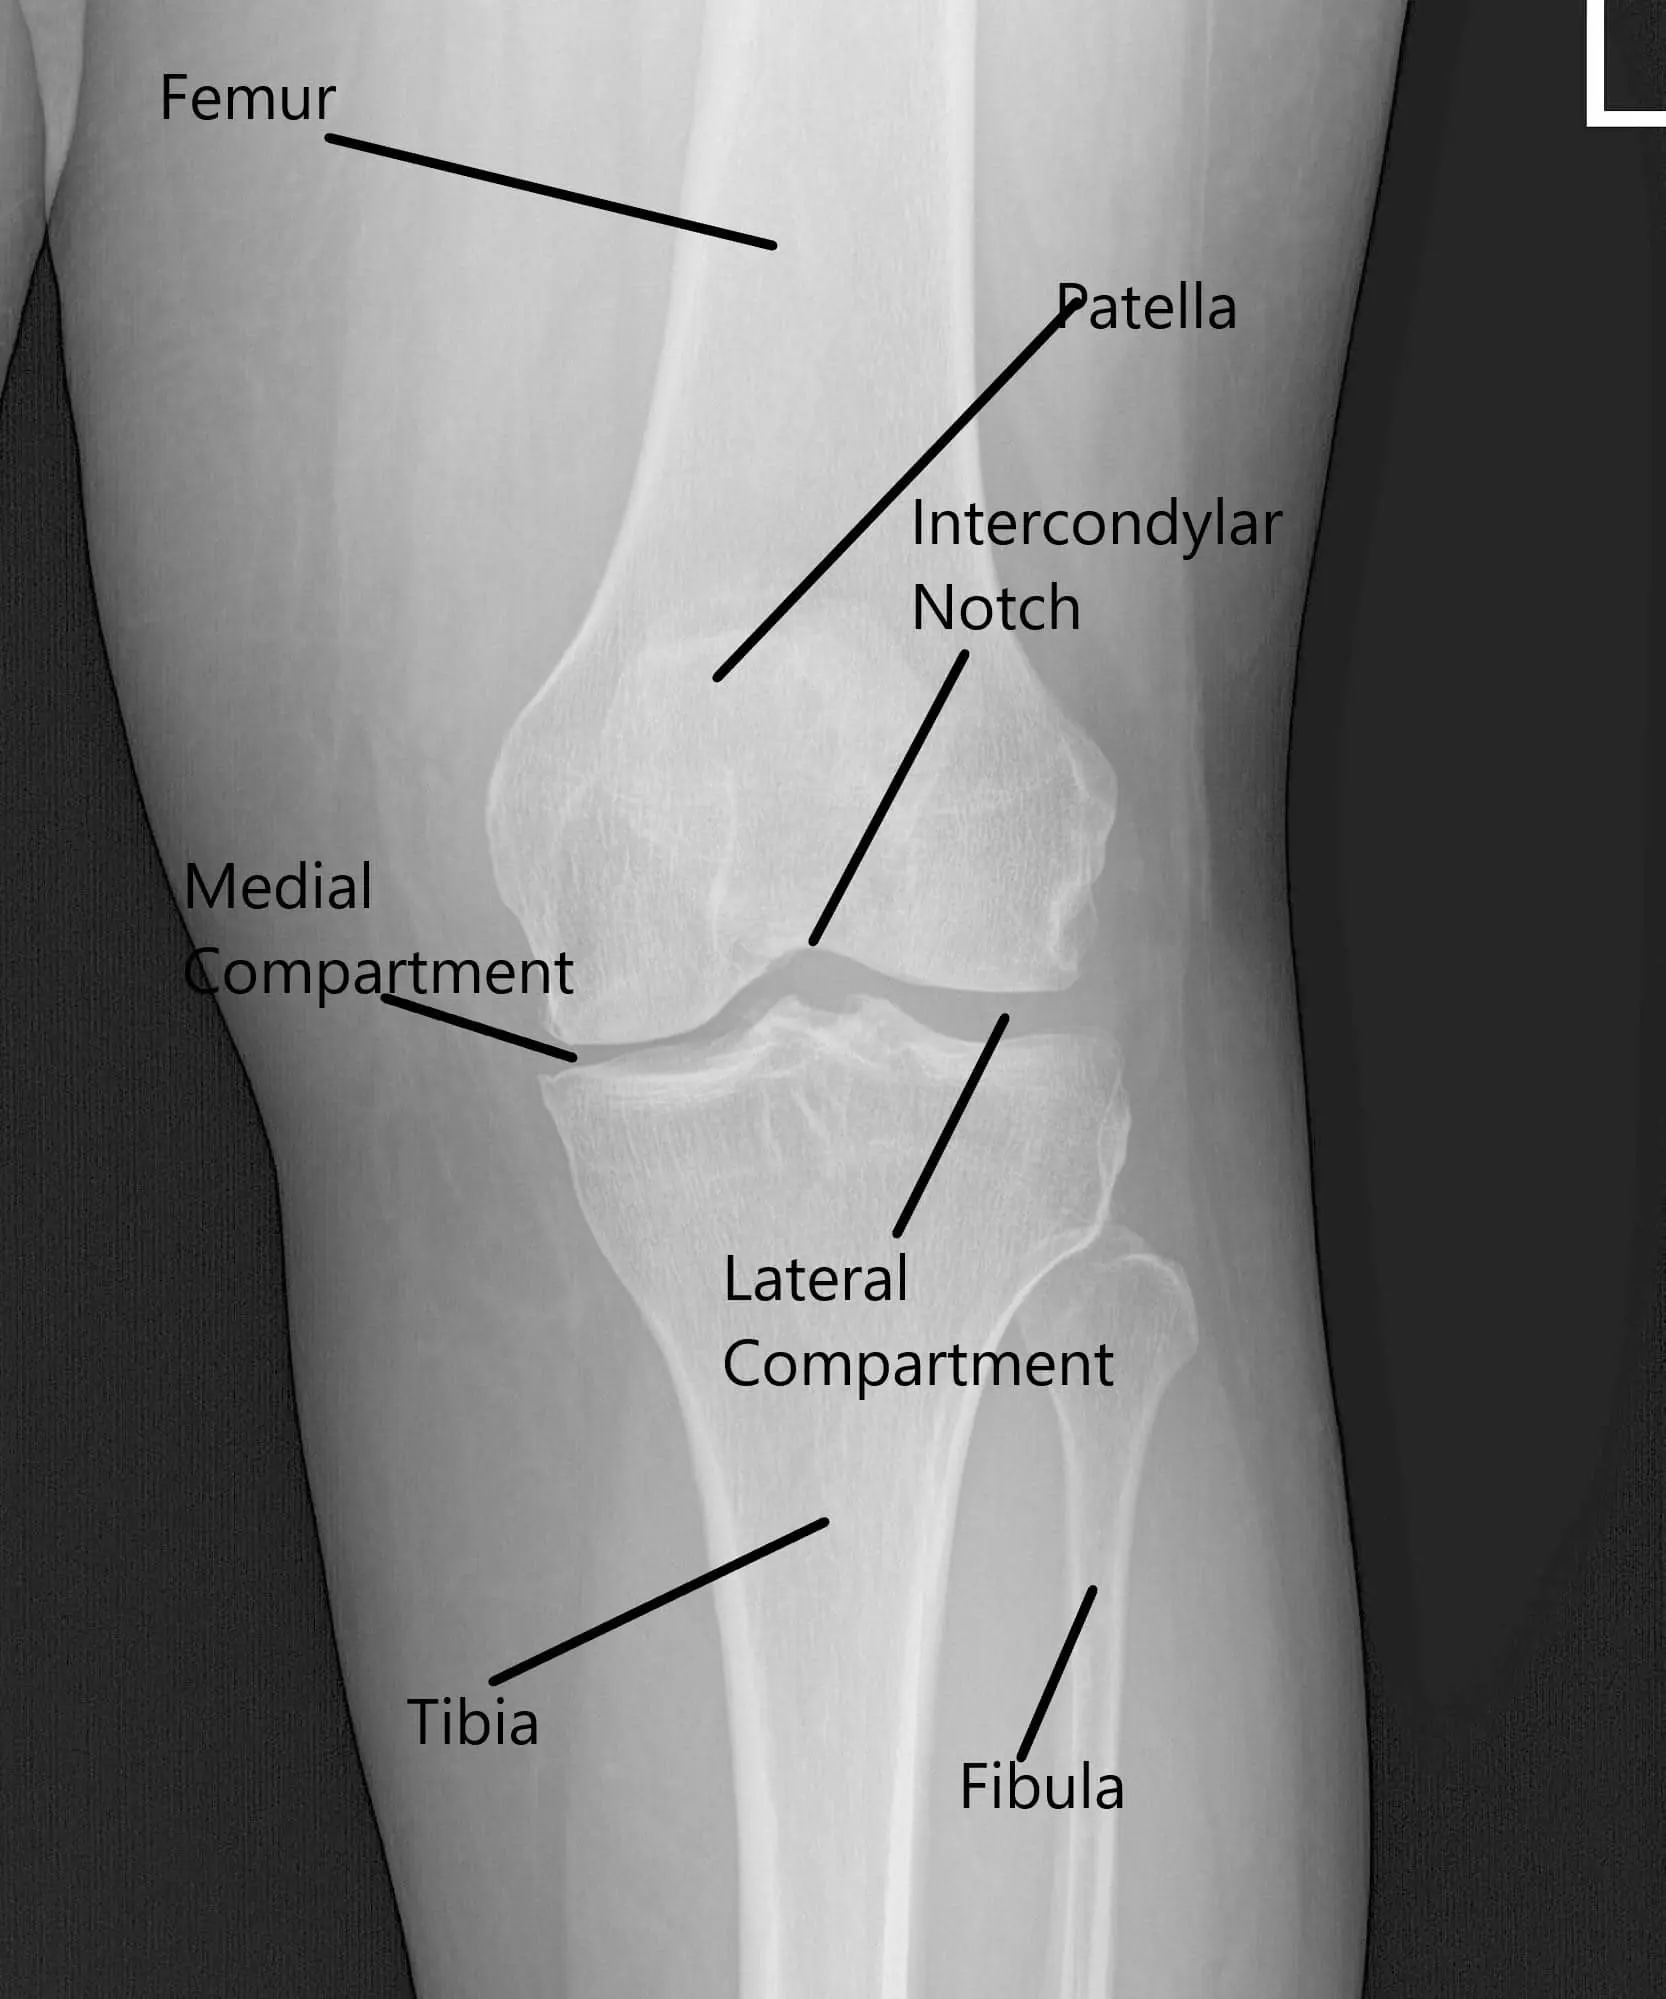

X-ray of the left knee showing AP and Lateral views.